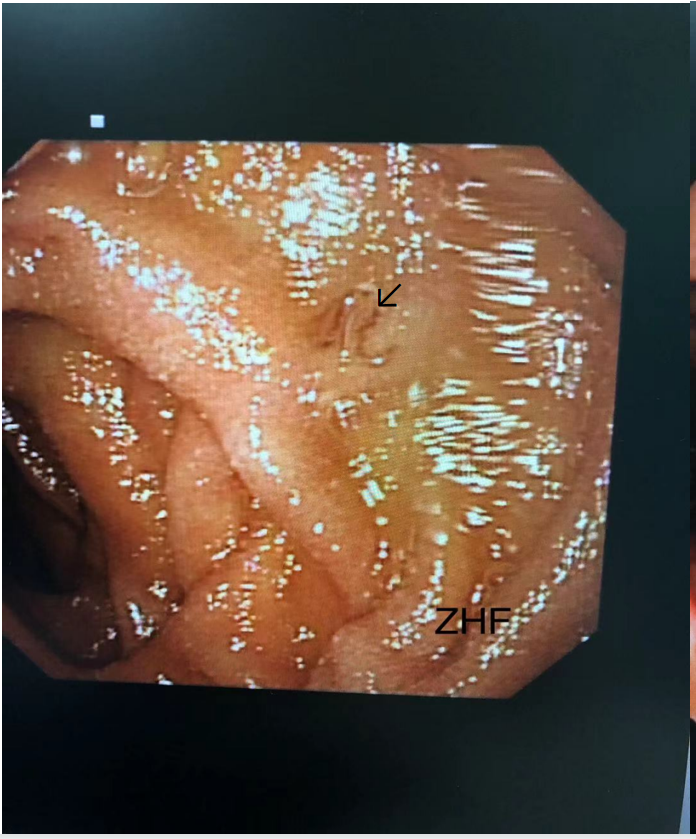

胃镜检查影像

钩虫成虫特点:

活体呈肉红色,长约1CM。

死后呈灰白或乳白色。

镜下:

头部:有大而深的口囊,有两对腹齿,一对外齿大于一对内齿,在口囊背缘正中线缺口较深,呈U形,背侧有一对三角形板齿。

尾部:雌虫有尾刺;雄虫有交合伞。

鉴定为钩虫成虫是临床确诊的直接依据。